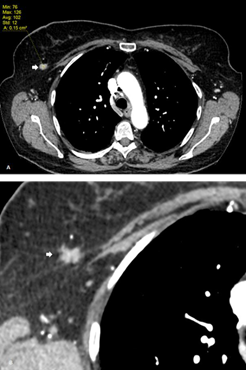

Some authors advocate that contrast-enhanced CT improves detection and characterization of breast lesions. Perrone et al. propose its use as an alternative to MRI in patients with usual contraindications such as incompatible pacemakers or surgical clips, severe dyspnea and claustrophobia. They recommend to acquire CT images at 1 minute after contrast administration and to apply a cutoff attenuation value of 90 Hounsfield units that would allow to differentiate between benign and malignant lesions (Figure 3).20 Inoue an al. demonstrate that the use of dynamic contrast-enhanced CT (DCE-CT) like DCE-MRI, can be useful to identify and to characterize breasts lesions. In their protocol, acquisitions were obtained at 1, 3, and 8 minutes after intravenous contrast injection. On time-density curve analysis, the washout pattern had a positive predictive value for breast malignancy of 93%, with a sensitivity of 91%.21 Morphological criteria can also be implemented in order to distinguish malignant from benign lesions. Spiculated or hazy margins, irregular shape and rim enhancement can all be looked upon as reliable features of malignancy.6,21 Moreover, axillary lymphadenopathies, pectoralis muscle infiltration and pleural effusion strongly suggest tumoral invasion.6 In summary, contrast-enhanced CT scan seems to be a reliable alternative to MRI, with the advantages of being faster, particularly for dynamic studies, as well as less susceptible to movement artifacts.20 However, due to radiation exposure concerns, chest CT scan must be reserved for elderly patients.22

Figure 3 A. Follow-up contrast-enhanced chest CT in a patient with lung carcinoma shows an incidental right breast lesion with contrast enhancement up to 102 HU. B. Same image with smaller FOV (field-of-view) evidencing the spiculated and irregular borders. C. Digital mammography of the same patient showing an irregular lesion with blurred borders. D. Ultrasound imaging reveals a hypoechoic lesion with angulated borders associated with a hyperechoic halo.